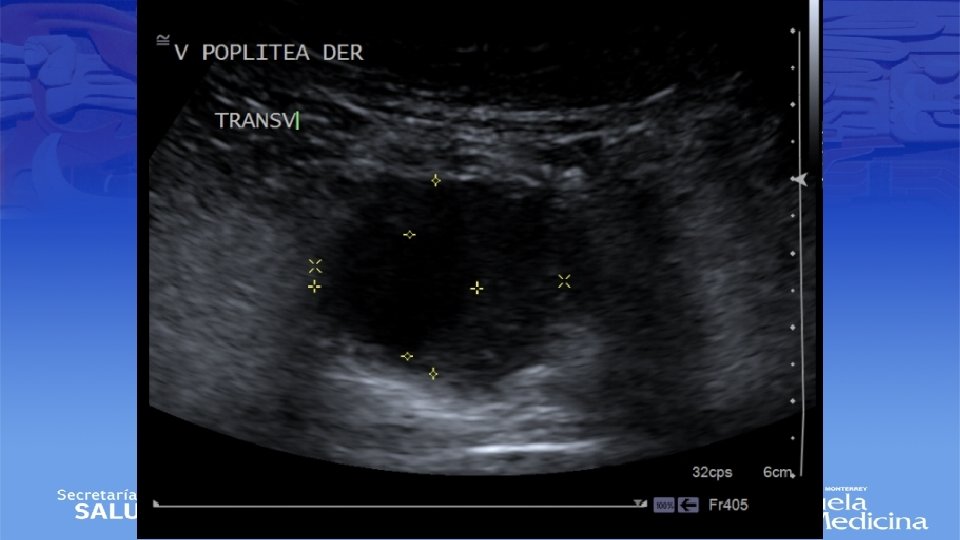

ECO Doppler

Impresión Diagnóstica • IDX: Aneurisma Poplíteo bilateral

Diagnostico • Ultrasonido Doppler, Angiotac, angioresonancia • Arteriografía es mas apropiada para sintomatología aguda